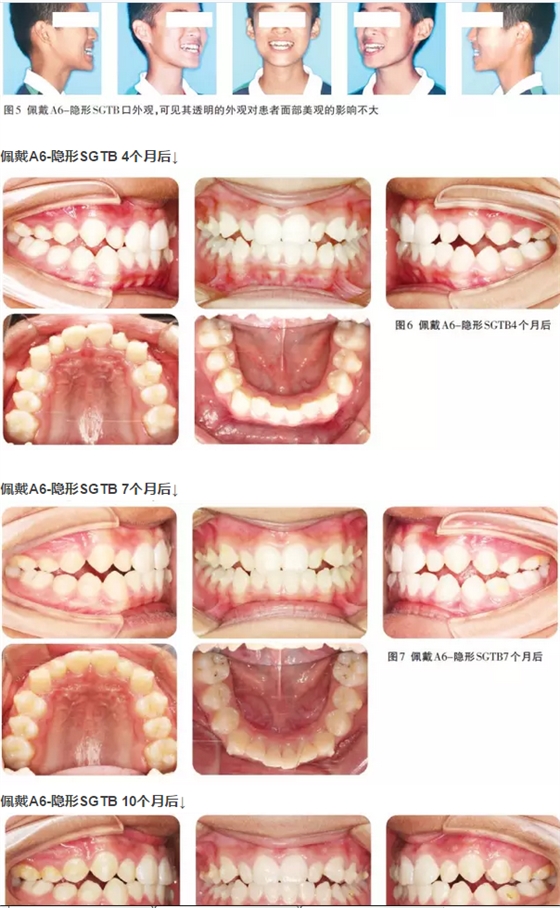

患者男性,13歲,主訴“牙齒歪斜”求治。面像及口內(nèi)像如圖1所示。